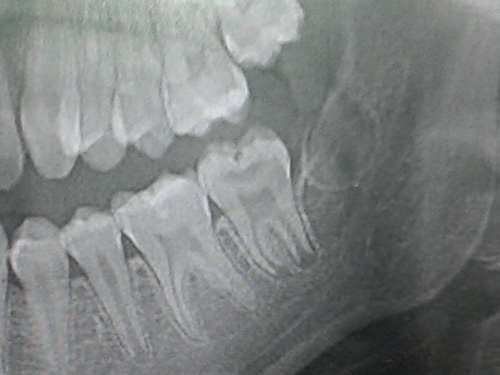

Marchena Rodríguez, Leticia. Máster en Salud Pública Oral. Universidad de Sevilla. Fernández Ortega, Carlos Mª. Máster en Salud Pública Oral. Universidad de Sevilla. RESUMEN La varicela es una enfermedad común en niños de 5 a 9 años, que generalmente se resuelve sin necesidad de tratamiento contra la misma. Las lesiones orales tradicionalmente asociadas a dicha enfermedad se producen sobre tejido blando, no son dolorosas y desaparecen a la conclusión de la enfermedad. No obstante, la varicela puede causar defectos permanentes en el esmalte si se contrae durante la etapa de calcificación de la dentición permanente, en particular los primeros molares. El presente artículo realiza una revisión bibliográfica del tema, a la vez que presenta un caso clínico de un paciente con defectos en el esmalte, causados posiblemente por la varicela. Al no existir abundante bibliografía sobre el asunto, se recomienda perseverar en la investigación de la posible relación causal entre varicela y defectos en el esmalte. Palabras clave Varicela, manifestación oral, virus varicela-zoster, herpes-zoster, hipomineralización. ABSTRACT Varicella is a common illness in children 5 to 9 years, which usually resolves without treatment against it. Oral lesions traditionally associated with this disease occur on soft tissue, are not painful and disappear at the conclusion of the disease. However, Varicella can cause permanent enamel defects if contracted during the period of calcification of the permanent teeth, including first molars. This paper makes a review of the literature, while presenting a case of a patient with enamel defects possibly caused by Varicella. Since there is abundant literature on the subject, it encourages continued research into the possible causal relationship between chickenpox and enamel defects. Key words Varicella, oral expression, varicella-zoster, herpes zoster, Hypomineralization virus. INTRODUCCIÓN Etiología La varicela es una enfermedad vírica causada por el virus Varicela-Zoster (VVZ), o herpesvirus 3 en humanos. Si bien la infección primaria se manifiesta habitualmente en niños y adolescentes, no es extraño que en algunos pacientes inmunodeprimidos que ya han estado expuestos al VVZ con anterioridad dicho virus se reactive en forma de Herpes-Zoster o Varicela-Zoster. (1, 2) El virus se transmite principalmente a través de partículas de saliva, así como por contacto con cierta cantidad de partículas virales. Ello da lugar a dos situaciones particularmente comprometidas en la consulta dental en lo que se refiere a transmisión de la enfermedad; por un lado, el spray utilizado en la consulta puede actuar como medio de transmisión de las mencionadas partículas; por otro, el contacto del dentista con las vesículas causadas por la varicela, con alta carga vírica, puede ocasionar una transmisión accidental de la enfermedad a otro paciente o a sí mismo. (3) Patogenia Tras el contagio tiene lugar una replicación viral en los ganglios linfáticos regionales, con una duración aproximada de 2 a 4 días. A continuación se produce una viremia inicial, que dura de 4 a 6 días. Posteriormente se da una segunda replicación en el hígado y el bazo, entre otros órganos, seguida de una segunda viremia. Algunos autores sostienen que en esta fase el virus se extiende a los nervios sensoriales, donde permanece en estado latente. La reactivación del virus daría lugar al Herpes Zoster. (1, 4) Características clínicas Los síntomas que se manifiestan durante el período prodrómico incluyen, entre otros, fiebre, cefalea, malestar general, congestión pulmonar o dolor faríngeo. (5, 6). A continuación se produce la manifestación más característica de la enfermedad, consistente en una erupción cutánea general de máculas eritematosas, que a su vez evolucionan a pápulas, vesículas y pústulas. Por otro lado, el hecho de que puedan coincidir lesiones en distinta fase de desarrollo es una de las características más destacadas de la enfermedad. (7) Diagnóstico La enfermedad plantea un diagnóstico diferencial con el síndrome boca-mano-pie o la primoinfección herpética (herpes simple). (8). A nivel bucal, en caso de lesión simple puede hacerse un diagnóstico diferencial con la estomatitis aftosa recurrente menor. Si se producen lesiones múltiples se plantea un diagnóstico diferencial con la primoinfección herpética. Usualmente la varicela se diagnostica por las características clínicas, tales como la erupción cutánea, así como la información obtenida en la anamnesis en relación con la exposición al virus. No obstante, en caso necesario existen técnicas de diagnóstico tales como la citología del contenido de las vesículas, inmunfluorescencia directa de una biopsia, reacción en cadena de la polimerasa o cultivos. (3, 8, 9) Complicaciones La varicela presenta una serie de complicaciones en adultos y pacientes inmunodeprimidos que la hacen más peligrosa, tales como la neumonía, la encefalitis, fiebre a altas temperaturas, infección secundaria de las lesiones o síndrome de Reye. En pacientes inmunodeprimidos, sin una terapia antiviral efectiva, puede producirse la muerte en un porcentaje comprendido entre el 7% y el 20%. (1, 10, 11, 12) Adicionalmente, la infección por VVZ durante el embarazo supone un peligro para el feto (13, 14). Epidemiología y vacuna La varicela es una de las enfermedades más comunes que pueden suceder durante la infancia. Así, el 90% de los adultos presenta anticuerpos del VVZ. La edad típica de infección se sitúa entre los 5 y los 9 años de edad. La incidencia de Herpes-Zoster es reducida, situándose en el 0,074% para menores de 9 años, en el 0,1% para los pacientes entre 10 y 15 años y entre el 0,3% y el 0,5% para la población adulta. Actualmente existe vacuna eficaz contra la varicela, que puede administrarse en una dosis única a partir de los 15 meses de vida, o en dos dosis para adultos (2). Además, la prevalencia de herpes-Zoster en niños sanos vacunados es aún más reducida de lo descrito con anterioridad. No obstante, dicha vacuna está contraindicada en pacientes inmunodeprimidos y mujeres embarazadas. (1, 3, 4, 15, 16). Lesiones orales Las lesiones orales poseen inicialmente naturaleza vesicular y tamaño reducido, y se manifiestan principalmente en lengua, carrillo, paladar duro, encías y pilares posteriores. En una fase posterior se produce la rotura de las mismas, quedando una úlcera que en general presenta poco o ningún dolor. Las lesiones son a menudo similares a la de aftas menores recurrentes. En los casos en que se producen lesiones múltiples puede parecer que se trata de una lesión mayor. La principal área de apariencia de éstas es el bermellón del labio, seguida del paladar. (1, 5, 6, 17, 18) Asociación con la hipomineralización incisivo-molar La hipomineralización incisivo-molar es una patología que afecta fundamentalmente, aunque no de manera exclusiva, a los primeros molares permanentes, y se caracteriza por un defecto cualitativo en el esmalte causado por alteraciones en la calcificación de los mismos. Entre las posibles causas de la hipomineralización se encuentra la varicela. (19) OBJETIVO El presente artículo realiza una revisión bibliográfica del material existente acerca de la varicela y sus manifestaciones orales. Adicionalmente, se analiza un caso clínico que plantea una hipótesis de lesiones en el esmalte dental causadas por la varicela. MATERIAL Y MÉTODOS Se ha hecho una revisión bibliográfica en PubMed, Scopus; insertando palabras clave como "varicela, manifestación oral, virus varicela-zoster, herpes-zoster, hipomineralización". Se han seleccionado aquellas fuentes bibliográficas con una antigüedad menor a 15 años. Además, se desarrolla un caso clínico de lesiones en el esmalte dental, con la varicela como posible causa. RESULTADOS Paciente de sexo masculino de 13 años de edad que acude a la consulta dental para una exploración bucodental. El paciente refiere sensibilidad al frío y calor asociado a los 2ºmolares permanentes inferiores derecho e izquierdo, 47-37 semiincluidos. En la anamnesis preguntamos por su hábitos higiénico-dietéticos y comenta que se cepilla una vez al día los dientes y que come bebidas carbonatas los fines de semana. A nivel médico, la madre refiere que no toma ningún medicamento, lo único que comenta que hace unos 5 años pasó la Varicela; que le causó fiebre y malestar general, acompañado de lesiones máculo-papulosas a nivel cutáneo, sobre todo en brazos y espalda. Tras la exploración bucodental apreciamos caries limitadas a esmalte en 46 y 44 y la presencia de 2º molares permanentes mandibulares, 37,47 semiincluídos; en el que se aprecia en las cúspides vestibulares erupcionadas, defectos de hipomineralización del esmalte de estos molares; en los que el paciente refiere sintomatología dolorosa al frío y calor. Para completar el diagnóstico prescribimos una ortopantomografia de control para valorar el estado de estos 2º molares permanentes inferiores semiincluidos. Apreciamos en la radiografía en el 2º molar permanente inferior derecho, 47, defectos estructurales amelodentinarios con grave compromiso pulpar; apreciándose retracción del cuerno pulpar mesial debido a estos defectos de mineralización. La misma afectación amelodentinaria pero de menor gravedad se presenta en el 2º molar permanente inferior izquierdo, 37. En ambos molares permanentes, los ápices no se han terminado de formar, estando los ápices abiertos sin terminar su formación. Informamos a la madre de que posiblemente los defectos de hipomineralización en los 2º molares permanentes 37-47, pueden ser debidos a los hábitos higiénicos dietéticos y que también la afectación de la varicela hace 5 años, que coincide con las etapas de formación de estos 2º molares permanentes; puede haber contribuído a la aparición de defectos de hipomineralización molar. Recomendamos tratamiento conservador con la eliminación del tejido hipomineralizado y aplicación de relleno provisional con Óxido de Zinc Eugenol (IRM) para estimular así la formación de dentina terciaria; y que en el plazo de 3 meses acuda de nuevo a la consulta para la obturación definitiva a base de Amalgama de Plata. Motivamos al paciente a mejorar su higiene, cepillándose los dientes 3 veces al día y recomendamos también enjuagues con flúor. También vemos necesaria que cada 3 meses se aplique barniz de flúor, al catalogar al paciente en grave riesgo de caries.  Fig.1. Defectos de mineralización amelodentinario del 47 con afectación del asta pulpar mesial. Molar con ápices abiertos en estado todavía de formación radicular. Paciente con sensibilidad al frío y calor en el 47.  Fig.2. Defectos de mineralización amelodentinario en el 37 con sensibilidad al frío y calor; junto con ápices radiculares sin formar en un paciente que ha sufrido Varicela hace cinco años. DISCUSIÓN La varicela es una enfermedad de carácter benigno en la franja de los 5-9 años, que puede llevar asociadas complicaciones de importancia si se contrae en la edad adulta. La duración del período de incubación de la enfermedad es discutida. Algunos autores, como Fisher, sostienen que ésta se sitúa entre los 10 y los 21 días. Otros, como Bascones, la acotan entre los 14 y los 16 días. (2, 9) Las lesiones orales asociadas a la varicela presentan diagnóstico diferencial con la estomatitis aftosa recurrente, entre otras enfermedades, si bien las características clínicas en el resto del cuerpo permiten establecer el diagnóstico de varicela. Las lesiones asociadas no requieren tratamiento en la mayoría de los casos. La estomatitis aftosa recurrente (EAR) es considerada por muchos estudios como una posible característica clínica de la varicela. Sin embargo, existe un estudio reciente que no apoya la hipótesis del papel directo del VVZ en la patogénesis de EAR. Existe la teoría de que la varicela tiene consecuencias en el desarrollo de la dentición permanente, pudiendo dar lugar a defectos en el esmalte de la misma, si bien se trata de una hipótesis que requiere mayor investigación. El presente artículo ha expuesto un caso de hipomineralización del esmalte. En general los factores etiológicos de la hipomineralizción no se encuentran del todo definidos. (20) En el caso expuesto, la anamnesis practicada arroja la varicela como posible causa de la misma. No obstante, la revisión bibliográfica realizada ha encontrado muy pocos artículos relacionados. Se recomienda por tanto perseverar en la investigación de la posible relación causal entre varicela y defectos en el esmalte. CONCLUSIÓN La Varicela es una de las enfermedades víricas más frecuentes en los niños, por lo que es necesario conocer los signos y síntomas que producen a nivel general y también estar atentos antes las manifestaciones orales que aparecen; en concreto la hipomineralización incisivo-molar que puede estar implicada la Varicela como agente causal de la misma. Es fundamental que Médicos de Familia, Pediatras y Odontólogos traten de manera multidisciplinar a estos pacientes con Varicela, ya que sus manifestaciones clínicas no son sólo generales sino también presentan manifestaciones orales; que pueden necesitar un abordaje terapéutico precoz para tratarlos adecuadamente. BIBLIOGRAFÍA 1. Kolokotronis A, Louloudiadis K, Fotiu G, Matiais A. Oral manifestations of infections due to varicella zoster virus in otherwise healthy children. J Clin Pediatr Dent 2001;25(2):107-12. 2. Bascones A, Figuero E, Esparza G. Úlceras orales. Med Clin (Barc). 2005; 125(15): 590-7. 3. Lazarde L Janet, Arreaza I Alven, Lugo F María V, Osorio G Aura Y. Lesiones de varicela en cavidad bucal: reporte de un caso. Acta odontol. venez [revista en la Internet]. 2007 [citado 2014 Jul 20] ; 45(2): 283-286. Disponible en: http://www.scielo.org.ve/scielo.php?script=sci_arttext&pid=S0001-63652007000200031&lng=es 4. Papadopoulos AJ, Schwartz RA, Janniger CK. Chickenpox. Cutis. 2000; 65 (6): 1355-8. 5. Sapp JP, Eversole LR, Wysocki GP. Patología Oral y Maxilofacial Contemporánea. 1998. Harcourt Ed. Madrid. 6. Bascones Martínez A. Medicina bucal. 3ª ed. Barcelona: Ariel y Ediciones Avances; 2004. 7. Poulsen A, Cabral F, Nielsen J, Roth A, Lisse I, Aaby P. Growth, morbidity and mortality after chickenpox infection in young children in Guinea-Bissau. Journal of Infection. 2005;13:307-12. 8. Regezi JA, Sciubba JJ. Patología Bucal: correlaciones clinicopatológicas. México. 2000. Ed. McGraw-Hill. 9. Fisher RG, Edwars KM. Varicella Zoster. Pediatrics in Review. (1998); 19: 62-67. 10. Nee PA, Edrich PJ. Chickenpox pneumonia: case report and literature review. J Accid Emerg Med. 1999; 16(2): 147-50. 11. Arvin AM. Management of Varicella-Zoster Virus infections in children. Adv Exp Med Biol.1999; 458: 167-74. 12. Samonis G, Mantadakis E, Maraki S. Orofacial viral infections in the immunocompromised host. Oncol Rep.2000; 7(6): 1389-94. 13. Hartung J, Enders G, Chaoui R, Arents A, Tennstedt C, Bollmann R. Prenatal diagnosis of congenital Varicella syndrome and detection of varicella zoster virus in the fetus: a case report. Prenat Diagn.1999; 19(2): 163-6. 14. Sauerbrei A. Varicella Zoster virus infections in pergnancy. Inetervirology.1998; 41(4-5): 191-6. 15. Leung AK, Kao CP, Sauve RS. Scarring resulting from Chickenpox. Pediatric Dermatology. 2001; 18 (5): 378-380. 16. McCarry ML, Severson J, Tyring SK. Varicella Zoster Virus. Journal of the American Academy of Dermatology.1999; 41(1):1-14. 17. McIntyre GT. Viral infections of the oral mucosa and perioral region. Dent Update. 2001; 28(4): 181-6, 188. 18. Fenton SJ, Unkel JH. Viral infections of the oral mucosa in children: a clinical review. Pract Periodontics Aesthet Dent.1997; 9(6): 683-90; quiz 692. 19. García, L.; Martínez, eM. Hipomineralización Incisivo-Molar. Estado Actual. Cient Dent 2010;7;1:19-28. 20. Ferreira L, Paiva E, Ríos H, Boj J, Espasa E, Planells P. Hipomineralización incisivo-molar: su importancia en odontopediatría. odontol Pediátr 2005; 13: 54-59.